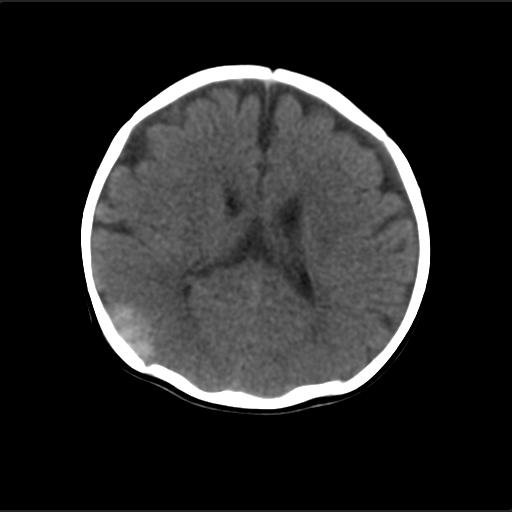

f2m出生已来可见右侧枕部见包块,质地软,无外伤史。包块处ct值16-67hu,大小约3.1x3.2cm左右。

局部颅骨破坏,并以破坏为中心的高密度肿块影,内示软骨影,考虑颅骨软骨瘤.

产伤?---骨膜下血肿机化?骨折?---外部性脑积水

仔细看颅骨是分离

骨质还算完整。

猜一个

考虑血肿的机化。

病灶位于颅缝区,向内外生长,边缘光整。考虑脑膜瘤

血肿机化可能性 比较大,伴双侧额颞顶部硬膜下积液。估计产伤引起